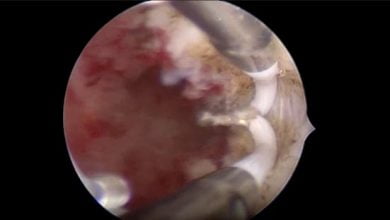

vNotes Hysterectomy – Cihan Kaya

Septum Rezeksiyonu

Tubal Polip

Vajinal Asiste Laparoskopik Seklaj Pektohisteropeksi – Dr. Çağlar Çetin

LİGHTED LS HİSTEREKTOMİ – Op. Dr. Seda ŞAHİN AKER